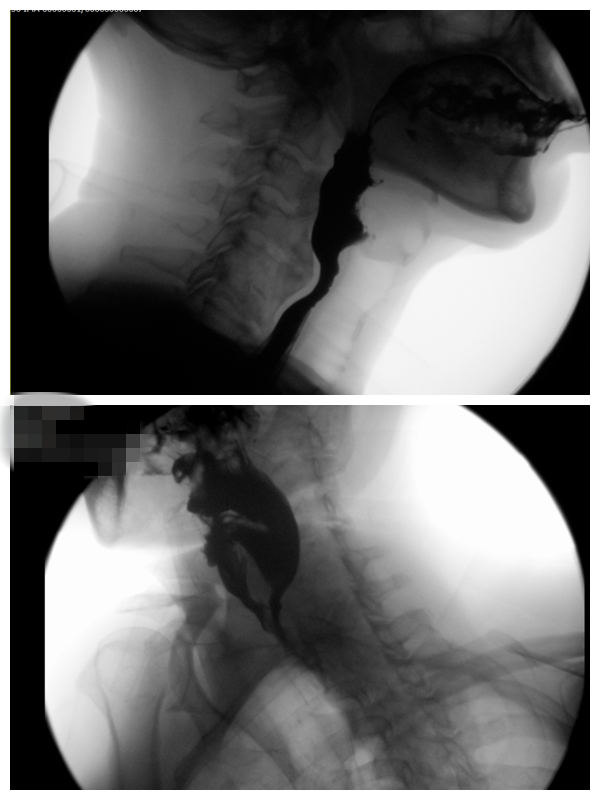

患者术前钡餐试验影像图

入院后,王晓飞让患者进行了颈椎X线、CT、MRI及食道钡餐造影检查,食管钡餐造影可见患者C4/5前缘食管狭窄及钡剂滞留征象。检查 结果出来后,患者被确诊为比较罕见的颈椎病——“食管型颈椎病”。若长此以往可能引起食道瘘引起致命性纵膈感染,严重影响患者的生活甚至生命。